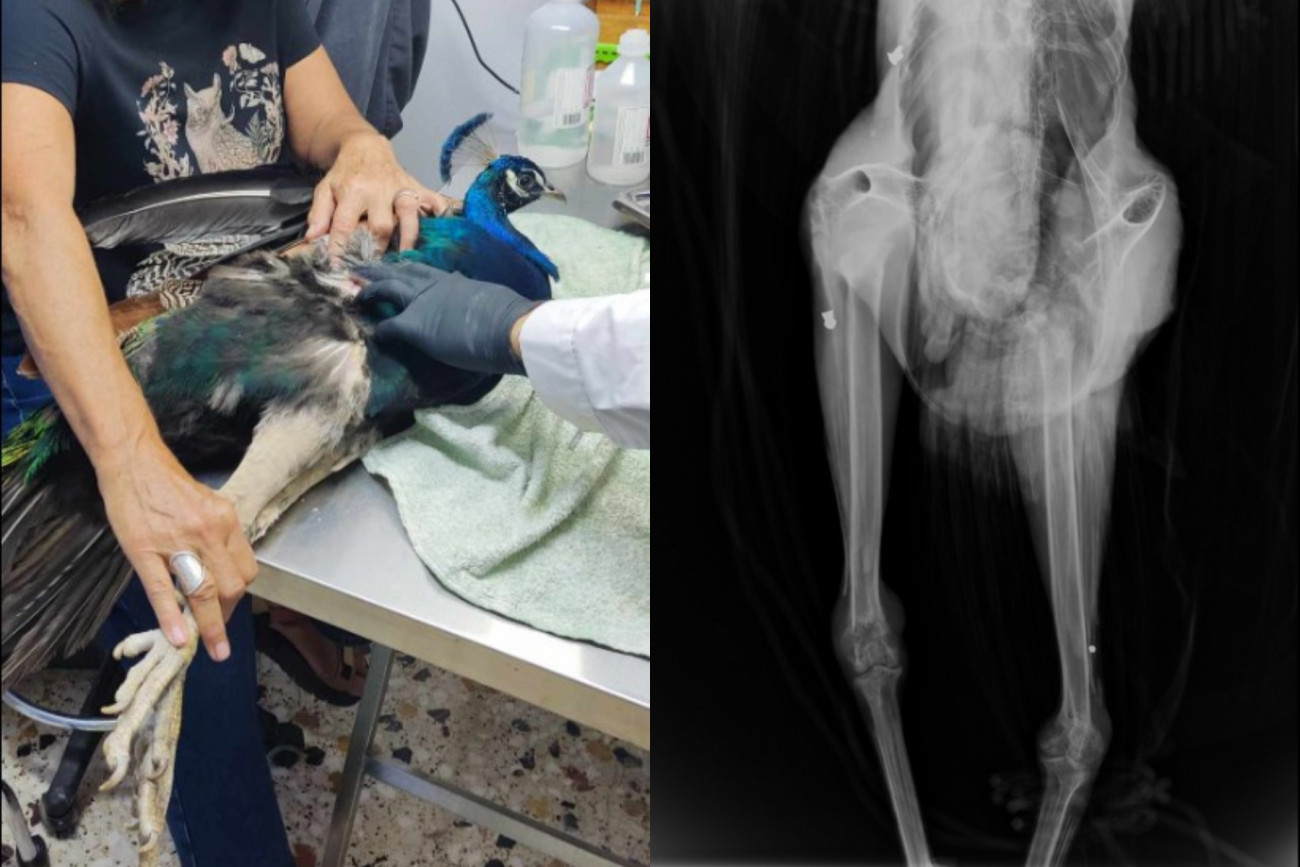

«Το παγώνι έχει πυροβοληθεί τρεις φορές, προς έκπληξή μας στην ακτινογραφία είδαμε δυο βολίδες αεροβόλου κι ένα σκάγι» αναφέρεται σε ανάρτηση του συλλόγου ΑΝΙΜΑ

Σε σχετική ανάρτηση του συλλόγου στο Facebook σημειώνεται: «Με έκπληξή μας, εμφανίζοντας την ακτινογραφία, είδαμε δυο βολίδες αεροβόλου κι ένα σκάγι μέσα στο σώμα του. Το ζώο αυτό έχει πυροβοληθεί τρεις φορές, την ίδια ώρα ή διαφορετικές δεν μπορούμε να ξέρουμε, ούτε αν ο δράστης είναι ένας ή δύο ή τρεις, μέσα ή δίπλα σε έναν από τους πιο πολυσύχναστους αρχαιολογικούς χώρους της Κρήτης και της Ελλάδας γενικότερα».

Η ακτινογραφία που έγινε στο παγώνι επειδή κούτσαινε αποκάλυψε τη φρίκη